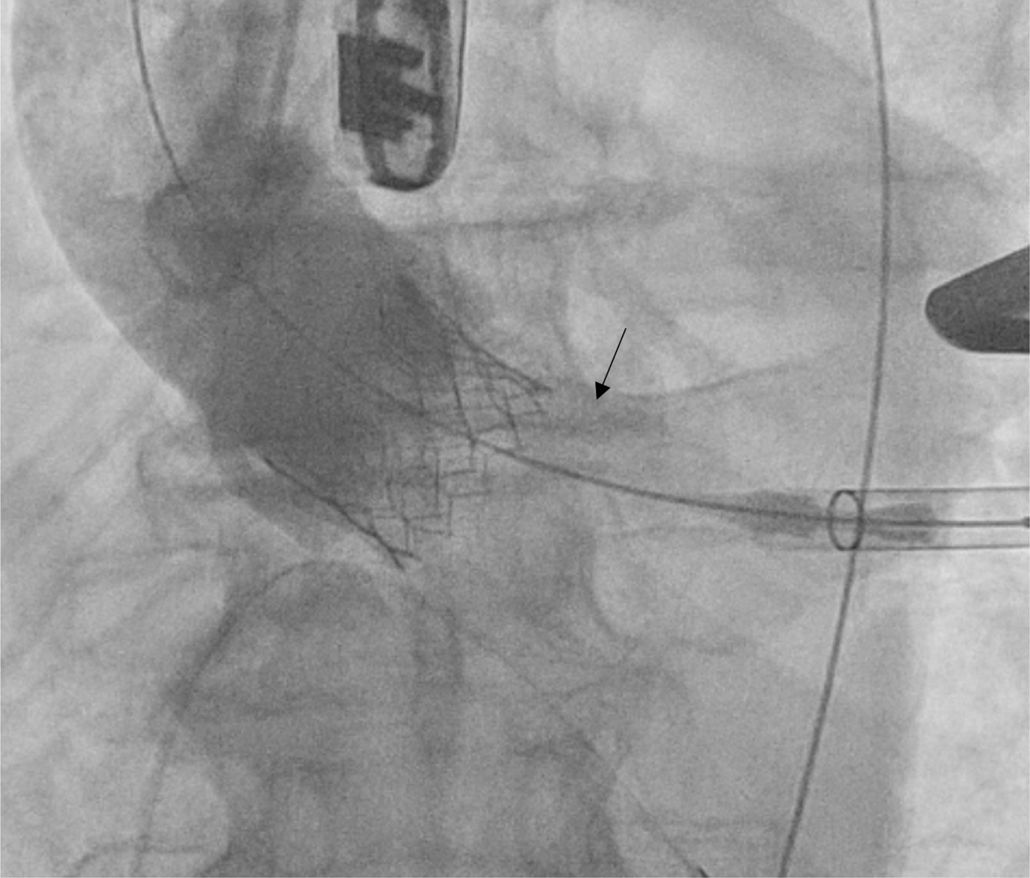

Existen numerosos escenarios que motivan el planteamiento de la post-dilatación tras el implante de una TAVI. Quizá el más importante (por su elevada frecuencia y repercusión negativa) sea la reducción de la severidad de una RPV, pues el baloneo promueve una expansión óptima de la prótesis (figs. 3 y 4). Con ello, también se consiguen un aumento del área valvular efectiva, una disminución de los gradientes y, en consecuencia, una reducción del mismatch (que se ha asociado a una mayor incidencia de trombosis valvular clínica y subclínica)46.

Regurgitación perivalvularLa RPV es consecuencia de una aposición incompleta de la prótesis al anillo nativo por intensa calcificación y excentricidad anular, infra, sobredimensión o posicionamiento inadecuado de la TAVI.

Li et al.49 realizaron un estudio computacional in vitro que simulaba el implante de una TAVI autoexpandible mediante dos modelos diferentes de dilatación (pre y post) con objeto de analizar su impacto en los resultados (estrés vascular, morfología del stent y RPV). Sus conclusiones argumentan que la pre-dilatación genera menor impacto que la post-dilatación, que puede mejorar la morfología protésica y, con ello, el funcionamiento y la durabilidad valvular. También optimizaría la adhesión al stent, con la subsiguiente reducción de la RPV en más del 30%.

La situación que más frecuentemente plantea la necesidad de post-dilatar es la existencia de una RPV (fig. 6). Quizá la envergadura de la misma (moderada/severa) sea uno de los factores más potentes, pero debemos atender también a otras características. Un paciente joven, de moderado/bajo riesgo, con anatomía favorable y sin comorbilidad o trastorno previo de la conducción se beneficiaría, sin duda, de la misma. También el implante de prótesis autoexpandibles, estenosis aórtica pura previa o aquellos casos en los que prima una gran durabilidad del implante.